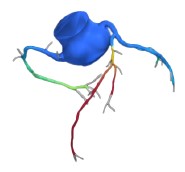

Traditional NITs vs. Heartflow | |||

Stress Echocardiogram | SPECT and PET | CCTA | Heartflow FFRCT Analysis |